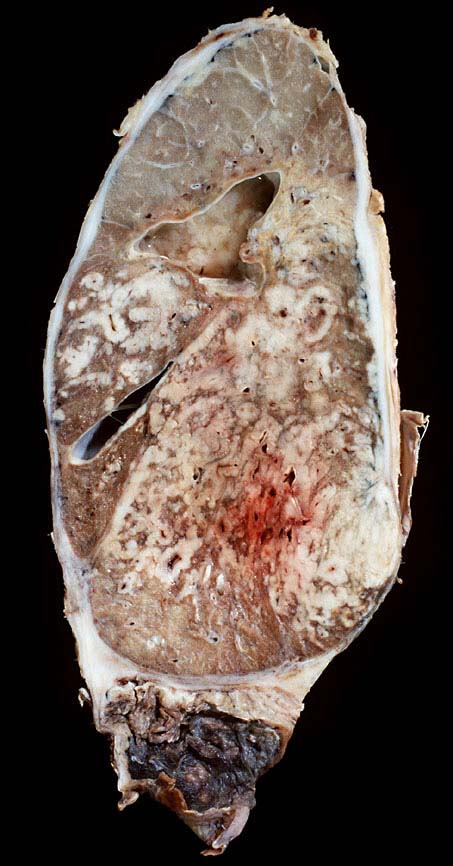

Kleinzelliges Bronchuskarzinom extensive disease

Ausgeprägte Lymphangiosis carcinomatosa und Tumorinfiltration der Pleura.

Nikotinabusus. COPD. Kleinzelliges Bronchuskarzinom, extensive disease. Chemotherapie und Radiotherapie.

Makroskopie